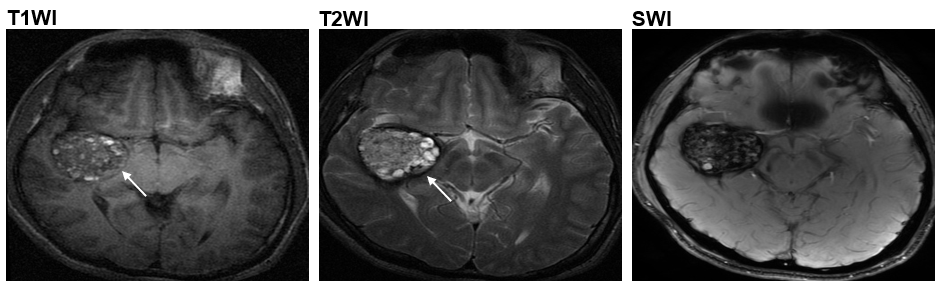

现时,磁力共振成像(MRI)是一种医生常用于诊断CCM的「非入侵性」方法。然而,MRI只能让医生知道血管瘤的大小及类别;至于是哪一个基因突变导致CCM,医生一般则只能透过手术以及化验得知。不过,科大研究团队设计了一个计算机程序,可以评估MRI 影像所显示的血管瘤与MAP3K3 c.1323C>G基因突变关系的概然率。因此,病人毋须「开刀」便得知是否存在MAP3K3 c.1323C>G基因突变,不但能减低施手术可能带来的脑出血或脑神经功能缺损等风险,亦可令病者及早展开更针对性的治疗。